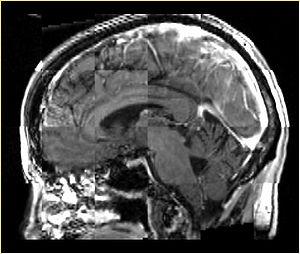

• Checkerboard appearance of unregistered images for the representative data of interest

• Case04